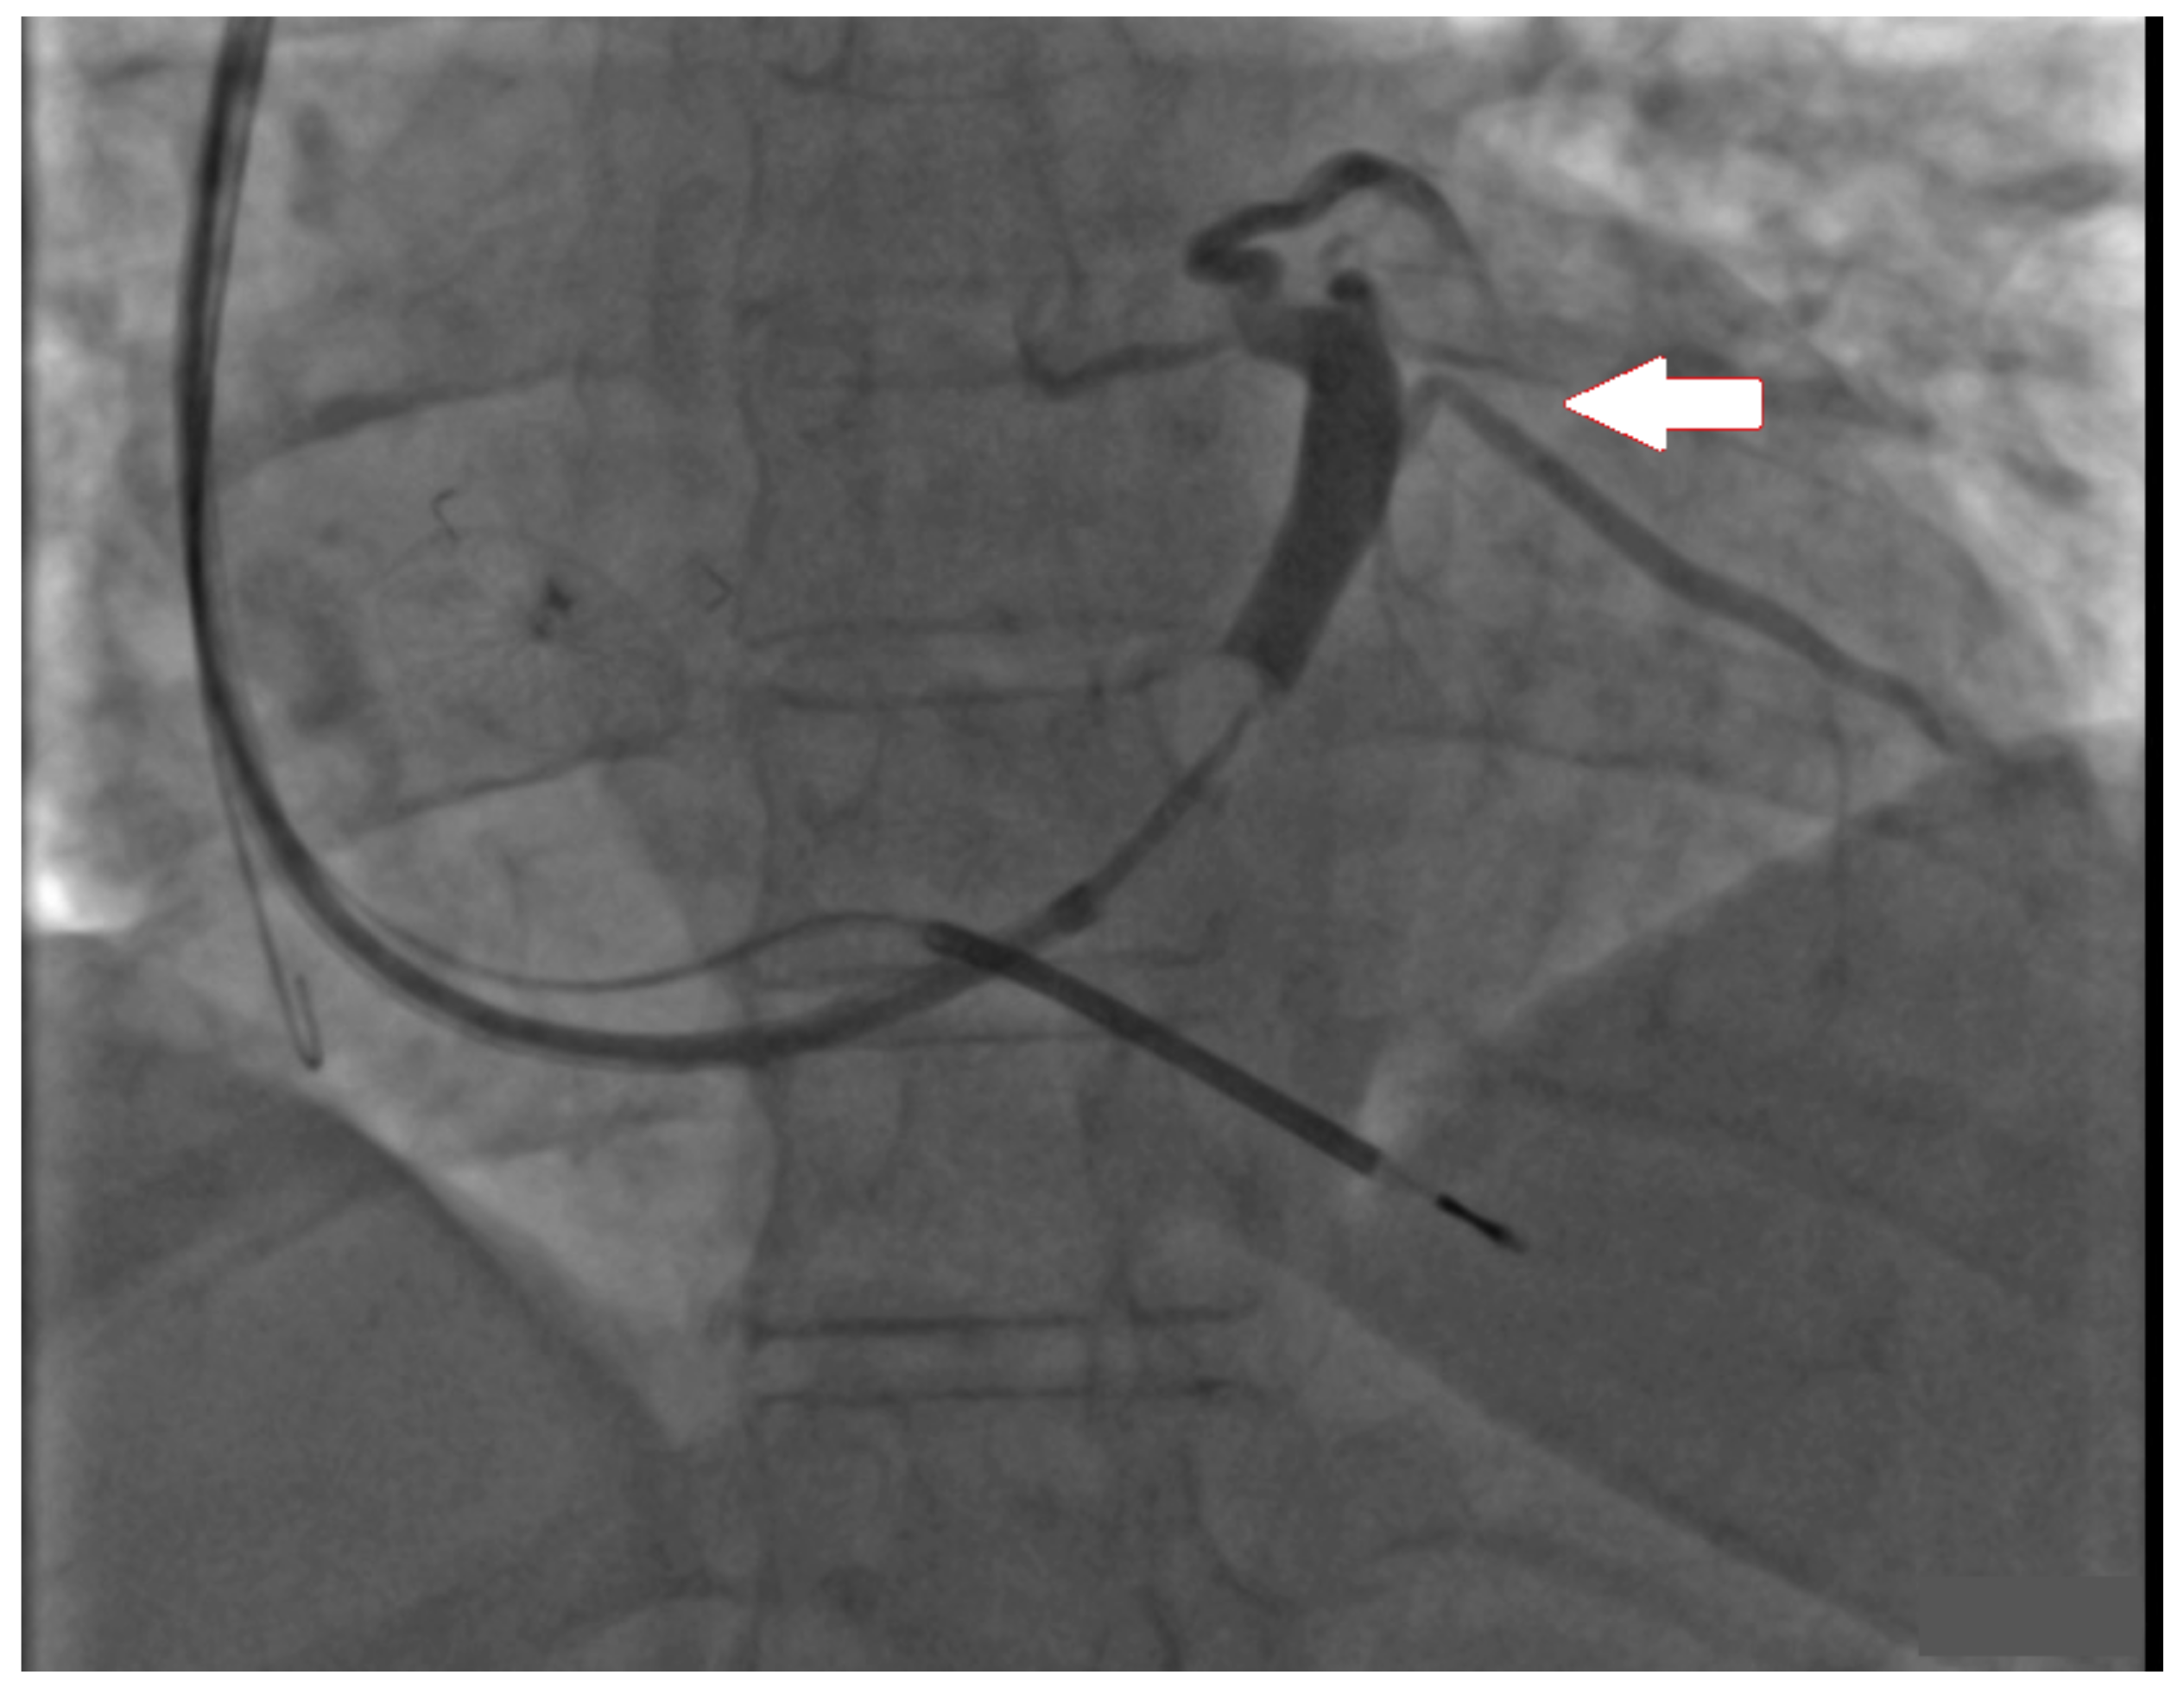

3. Case Report